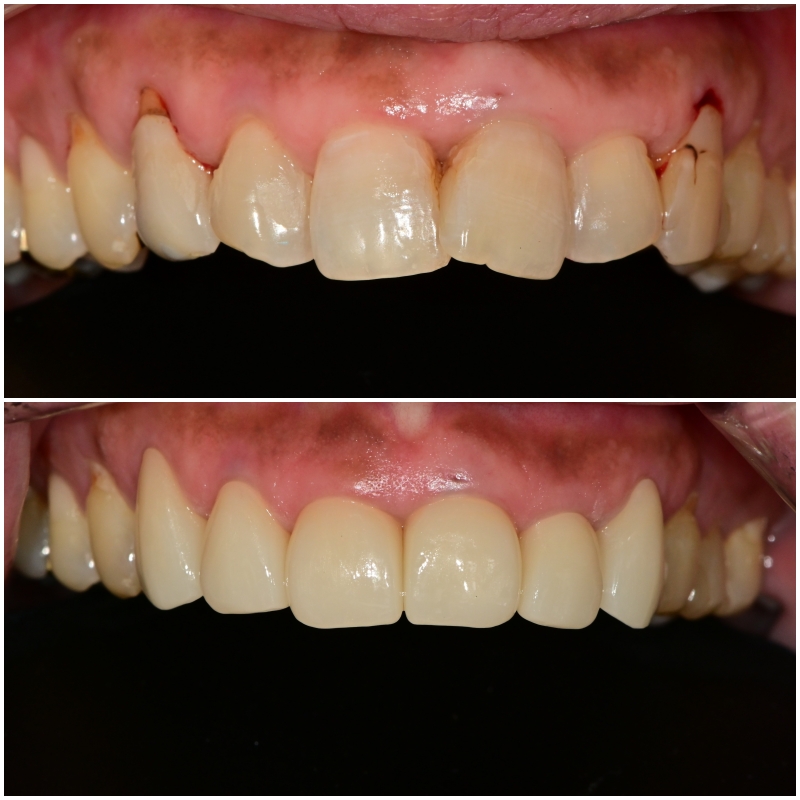

최종 보철물이 제작되어 적용이 되어있는 모델 상입니다

중간에 임시치아 제작 과정에서 애를 좀 먹었지만

저를 믿고 기다려주신 환자분께

최종 보철물은 아주 예쁘게 제작을 해드리기로 약속했습니다.

위에서 바라보았을 때도 전과 다르게

아주 이상적인 아치형을 그리고 있습니다,

정면에서 보았을 때도 정중선이 잘 맞고

치아가 대칭적으

로 형태도 맞으며 환자분께서

너무 밝지 않은 자연스러운 색상을 원하셔서

그 범위 내에서 밝은색으로 완성이 되었습니다.

이처럼 치열이 고르지 않은경우

보철에 의해서 결과는 드라마틱하게 좋아집니다.